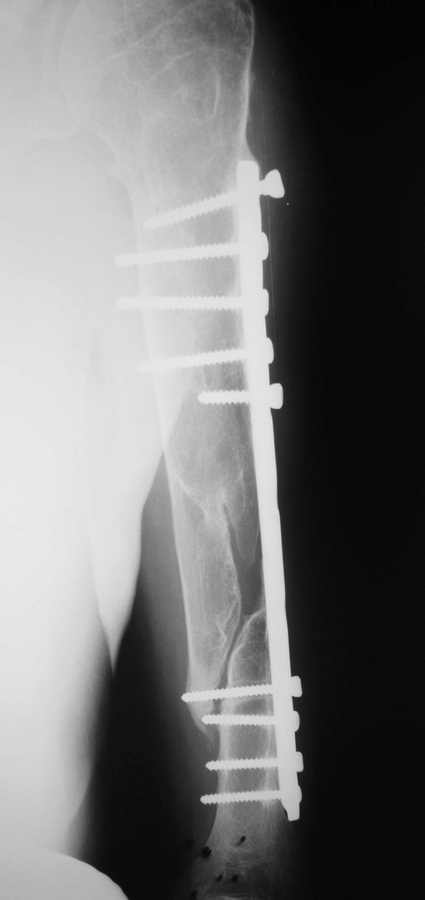

[Ortho] ложный сустав плеча.

Травма и операция два года назад.

Показан реостеосинтез. Выбор фиксатора?